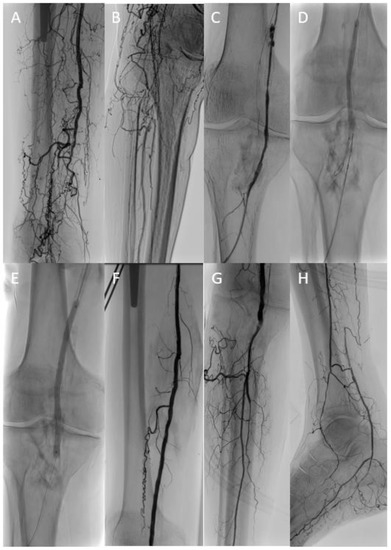

Figure 1.

Long occlusive lesion (A) with initially unsuccessful recanalization attempts via both the antegrade and retrograde (B) route. A target-balloon was inserted via the retrograde access and punctured with the re-entry needle of an Outback™ catheter (C,D). After predilatation with a standard balloon followed by drug coated balloon angioplasty (E), an acceptable result was achieved without the need for subsequent stent implantation (F).